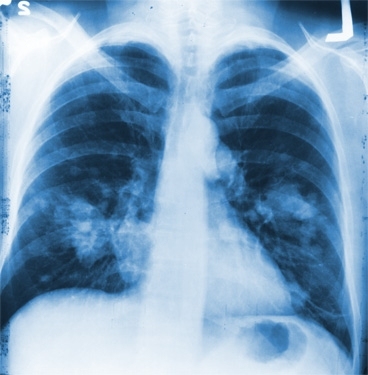

Using a new technique called whole-genome profiling, MIT scientists have now pinpointed a gene that appears to drive progression of small cell lung cancer, an aggressive form of lung cancer accounting for about 15 percent of lung cancer cases.

Small cell lung cancer kills about 95 percent of patients within five years of diagnosis; scientists do not yet have a good understanding of which genes control it. Dooley and her colleagues studied the disease’s progression using a strain of mice, developed in the laboratory of Anton Berns at the Netherlands Cancer Institute, that deletes two key tumor-suppressor genes, p53 and Rb.